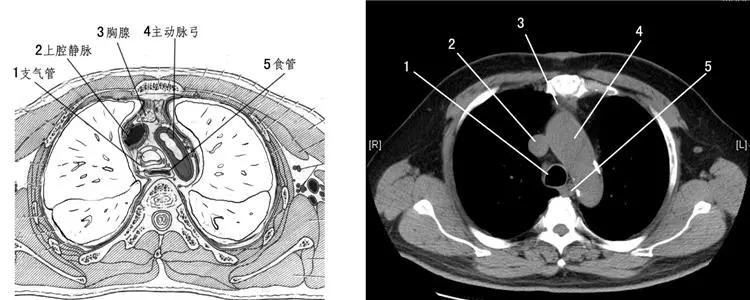

于是,我给阿叔开了心电图和心脏CT的单子,让他赶紧去做检查,不要耽误了治疗的时机。大约四十多分钟后,阿叔和女儿拿着检查报告回到了诊室,我拿起来一看心电图很正常、心脏CT看上去也很正常,可能冠脉会有些狭窄,但都不是事儿。